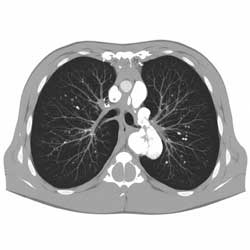

КТ дает послойное изображение легких в высоком разрешении. Исследование в разы информативнее рентгена и позволяет увидеть даже минимальные изменения в легочной ткани.

КТ помогает врачу точно определить локализацию и характер изменений и выбрать правильную тактику лечения.

В клинической практике КТ назначается, если данные рентгена недостаточны.

МСКТ — усовершенствованный вариант КТ, при котором используется несколько рядов детекторов. Это позволяет получить изображение за секунды, а детализация становится еще выше.

МСКТ особенно полезна при астме, ХОБЛ, интерстициальных заболеваниях легких и смешанных формах патологии.